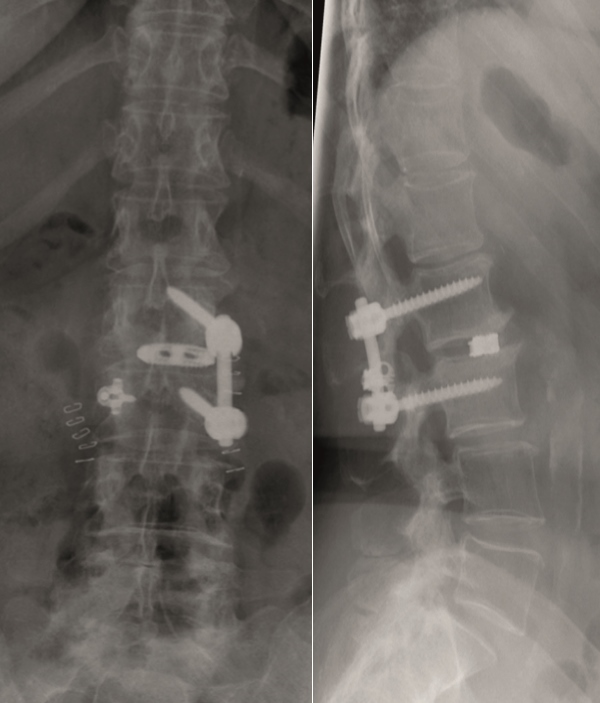

Case 5 : Degenerative scoliosis

A female patient 66-years-old with back pain, leg pain, and degenerative deformity. The x-rays show left convex degenerative scoliosis Cobb T12-L3 38. Nonoperative treatment failed. Treatment option was posterior fusion T11-L5, with URS Facet Wedge L2-L3 unilaterally.

A conventional approach for posterior correction was taken, with indirect Foraminal decompression and Facet Wedge fusion (apex curve). Facet Wedge introduction after curve correction with rod in situ. X-ray follow-up initially (Fig 20), with CT assessment of Facet Wedge fusion after 6 months (Fig 21).